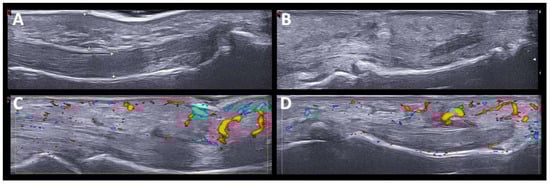

Five patients had a PMR-like syndrome. In three, the imaging test was made before the start of glucocorticoid treatment. US showed synovitis of the hip and trochanteric bursitis, and bilateral inflammatory bicep tenosynovitis, in one patient. In the other two patients, the shoulders and hip joints were studied by PET/CT scan, showing a periarticular pattern in the shoulder and pelvic girdle (see further comments below). We also identified sonographic changes in the wrists and hands in patients with PMR-like disease, affecting not only the wrists but also the MCPs, and finger tenosynovitis (Figure 2).

It has been reported that ICI-induced PMR has US and FDG-PET/CT results comparable to those seen in regular PMR [26]. We also found characteristic US findings in PMR-like ICI-induced patients similar to those previously described (i.e., glenohumeral and hip joint synovitis, bicipital tenosynovitis, and subacromial bursitis) [26]. Peripheral symmetrical synovitis and tenosynovitis, clinically subtle or not evident at all, in addition to rhizomelic involvement was a notable finding. Although peripheral synovitis and tenosynovitis are frequently reported in PMR, it is usually oligoarticular and transient [31]. As in other studies of typical PMR [32], we found that in patients with ICI-induced PMR, tenosynovitis of the flexor tendons of the hand was the most frequent US finding of peripheral involvement. Interestingly, in treated patients, we found not synovitis, tenosynovitis, or bursitis in the shoulders and pelvic girdles, which seemed to have resolved with glucocorticoid treatment. However, peripheral synovitis/tenosynovitis in the hand joints remained evident.

Figure 2. US findings in PMR-like pattern. (A). Hip joint (longitudinal view) with moderate effusion. (B). Bicipital tenosynovitis with power doppler signal grade 2. (C). Synovitis at second MCP joint with Power Doppler grade 2. (D). Tenosynovitis of hand flexor tendon with Power Doppler grade 2.